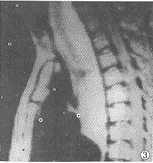

MRI检查: 食管中上段(T7以上)巨大香肠样软组织肿块,约27.0cm×6.5cm×5.2cm,T1 WI呈较均质等信号(图1、2),T2WI呈明显高信号(图3),肿块于主动脉弓附近尤为显著。M RI诊断:食管中上段占位性病变。

图1 横轴位T1WI示食管腔内等 信号软组织肿块,约6.3cm×5.2cm,前缘呈菜花状,气管受压向前推移 图2 矢状位T1WI示食管中上段软组织肿块,呈较均质等信号,边缘较清楚,大小约27.0 cm×6.5cm 图3 与图2相同层面,矢状位T2WI示食管中上段软组织肿 块呈高信号